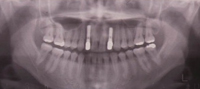

インプラント治療の症例(前歯多数欠損3)

50代 女性

治療前

前歯へのインプラントを希望された方です。

歯を抜いたあとにへこみが残ってしまっています。

治療中

歯肉の移植等も行ってから二本のインプラントを埋入しました。

治療後

レントゲンからも二本のインプラントがしっかりと埋入されていることがわかります。